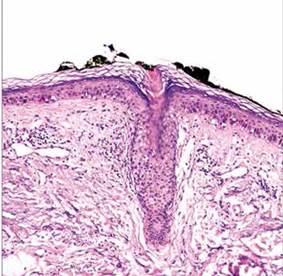

Se realizó biopsia cutánea incisional, cuyo estudio histopatológico fue concluyente con poroqueratosis actínica superficial diseminada, evidenciándose la presencia de una lámina cornoide característica(Figuras N° 3 y 4).

Figura N° 3. Tejido cutáneo con atrofia epidérmica, estrato basal con aumento de melanina y reacción de interfase vacuolar, dermis con elastosis solar difusa. Figura N°4. Se evidencia epidermis con paraqueratosis (lámina cornoide) dentro de una invaginación epidérmica, dermis con infiltrado infamatorio crónico.

El estudio histopatológico confirma el diagnostico, caracterizándose por la presencia de la lámina cornoide, una delgada columna de células paraqueratósicas dispuestas verticalmente sobre una depresión epidérmica, con ausencia o disminución de la capa granulosa y queratinocitos disqueratósicos o vacuolizados en la capa espinosa. En la dermis superior se observa un infiltrado inflamatorio linfocítico CD4+ de intensidad variable, a veces con características liquenoides, junto a vasos dilatados y ocasionales depósitos de amiloide.(5)) Estos hallazgos concuerdan con los observados en la biopsia de nuestra paciente, confirmando el diagnóstico de PASD.